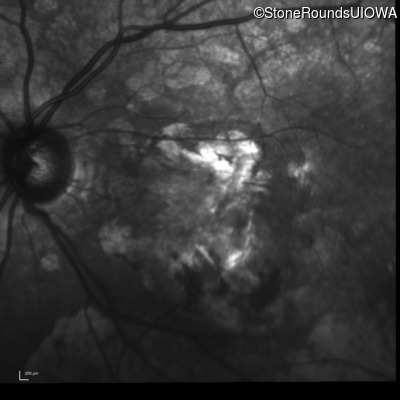

Infrared Fundus Photograph - Right - 20/200 +2

Exemplar